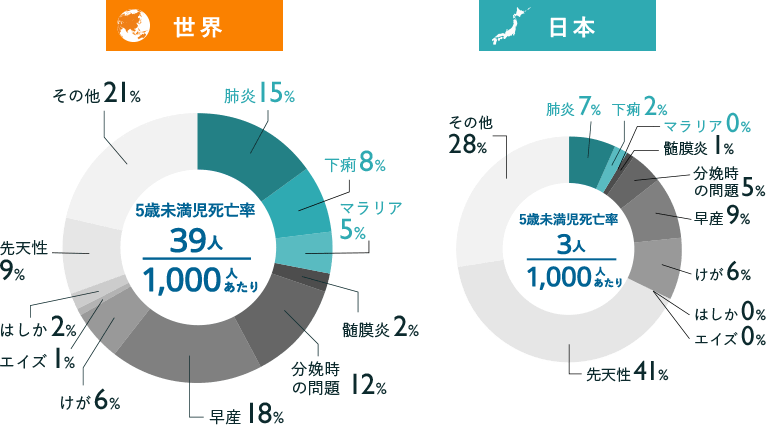

肺炎・下痢・マラリア。

いずれも先進国では治療も予防も可能な病気ですが、

世界ではこれら3つの病気だけで、

2017年の乳幼児死亡総数の約3割に相当する150万人以上が犠牲になっています。

その8割以上が集中するのは、

サハラ以南のアフリカと南アジアの貧しい国々の

世界でも貧しく厳しい環境で生きる子どもたちです。

※四捨五入しているため合計は100%になりません。

出典:UNICEF DATA (2017)

日本の医師の数は国民414人に対し1人。

一方、世界では数万人に対し医師1人という国も珍しくありません。

出典:WHO Global Health Observatory data repository (2016)